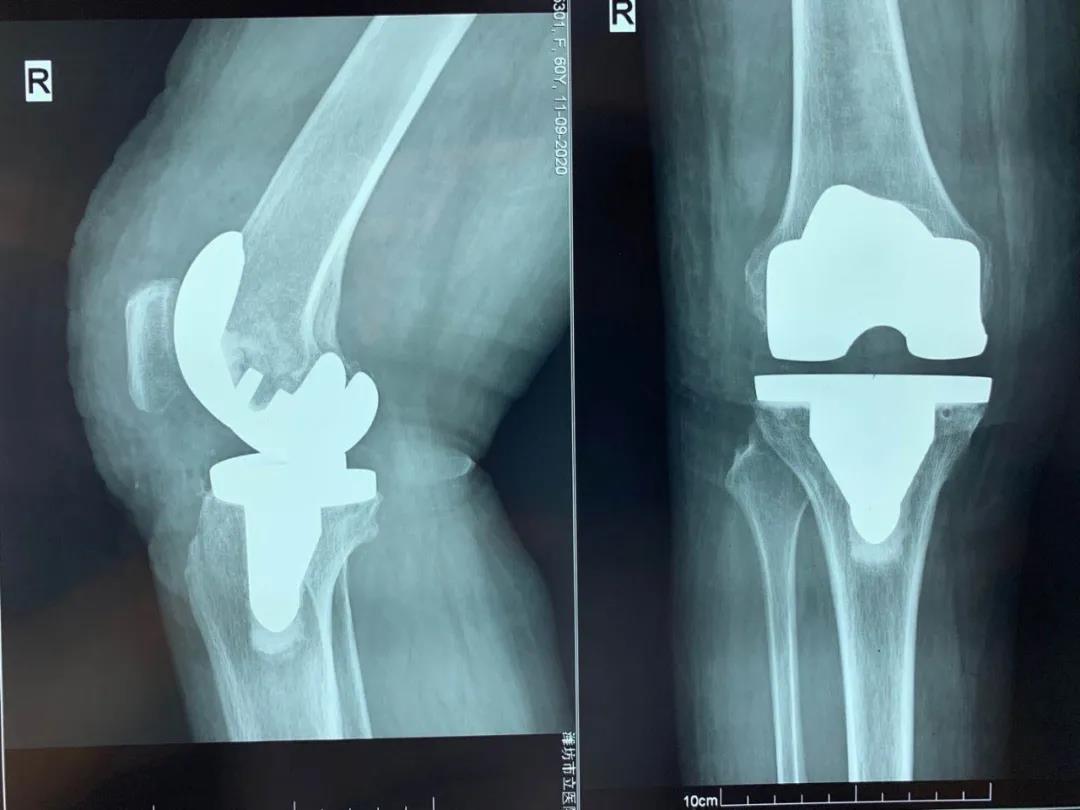

手術后